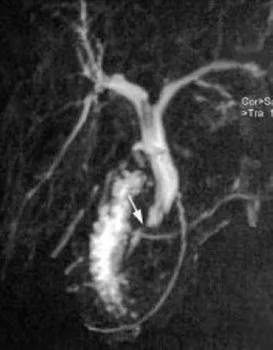

A

B

Figure 19. Jeune patiente ayant présenté un épisode de migration lithiasique, avec des calculs vésiculaires en échographie.Pendant la cholécystectomie, une cholangiographie peropératoire a montré une sténose cholédocienne. La bili-IRM (A) retrouve cette sténose, 15 mm en amont de la papille (flèche), avec dilatation de la VBP d’amont. On note par ailleurs un pancréas divisum, et la présence du drain biliaire en T laissé lors de la cholécystectomie. En IRM, aucune autre anomalie n’est notée en regard de la zone de sténose, y compris après injection de gadolinium. Ceci est confirmé par une échoendoscopie qui ne retrouve pas de syndrome de masse ni d’épaississement pathologique des parois biliaires. Une CPRE est réalisée dans le même temps (B) pour vérification cytologique par brossage et aspiration de bile, et mise en place d’une prothèse pour calibrage de la sténose. L’hypothèse retenue est celle d’une sténose bénigne, consécutive à une réaction inflammatoire sur lithiase enclavée puis secondairement évacuée